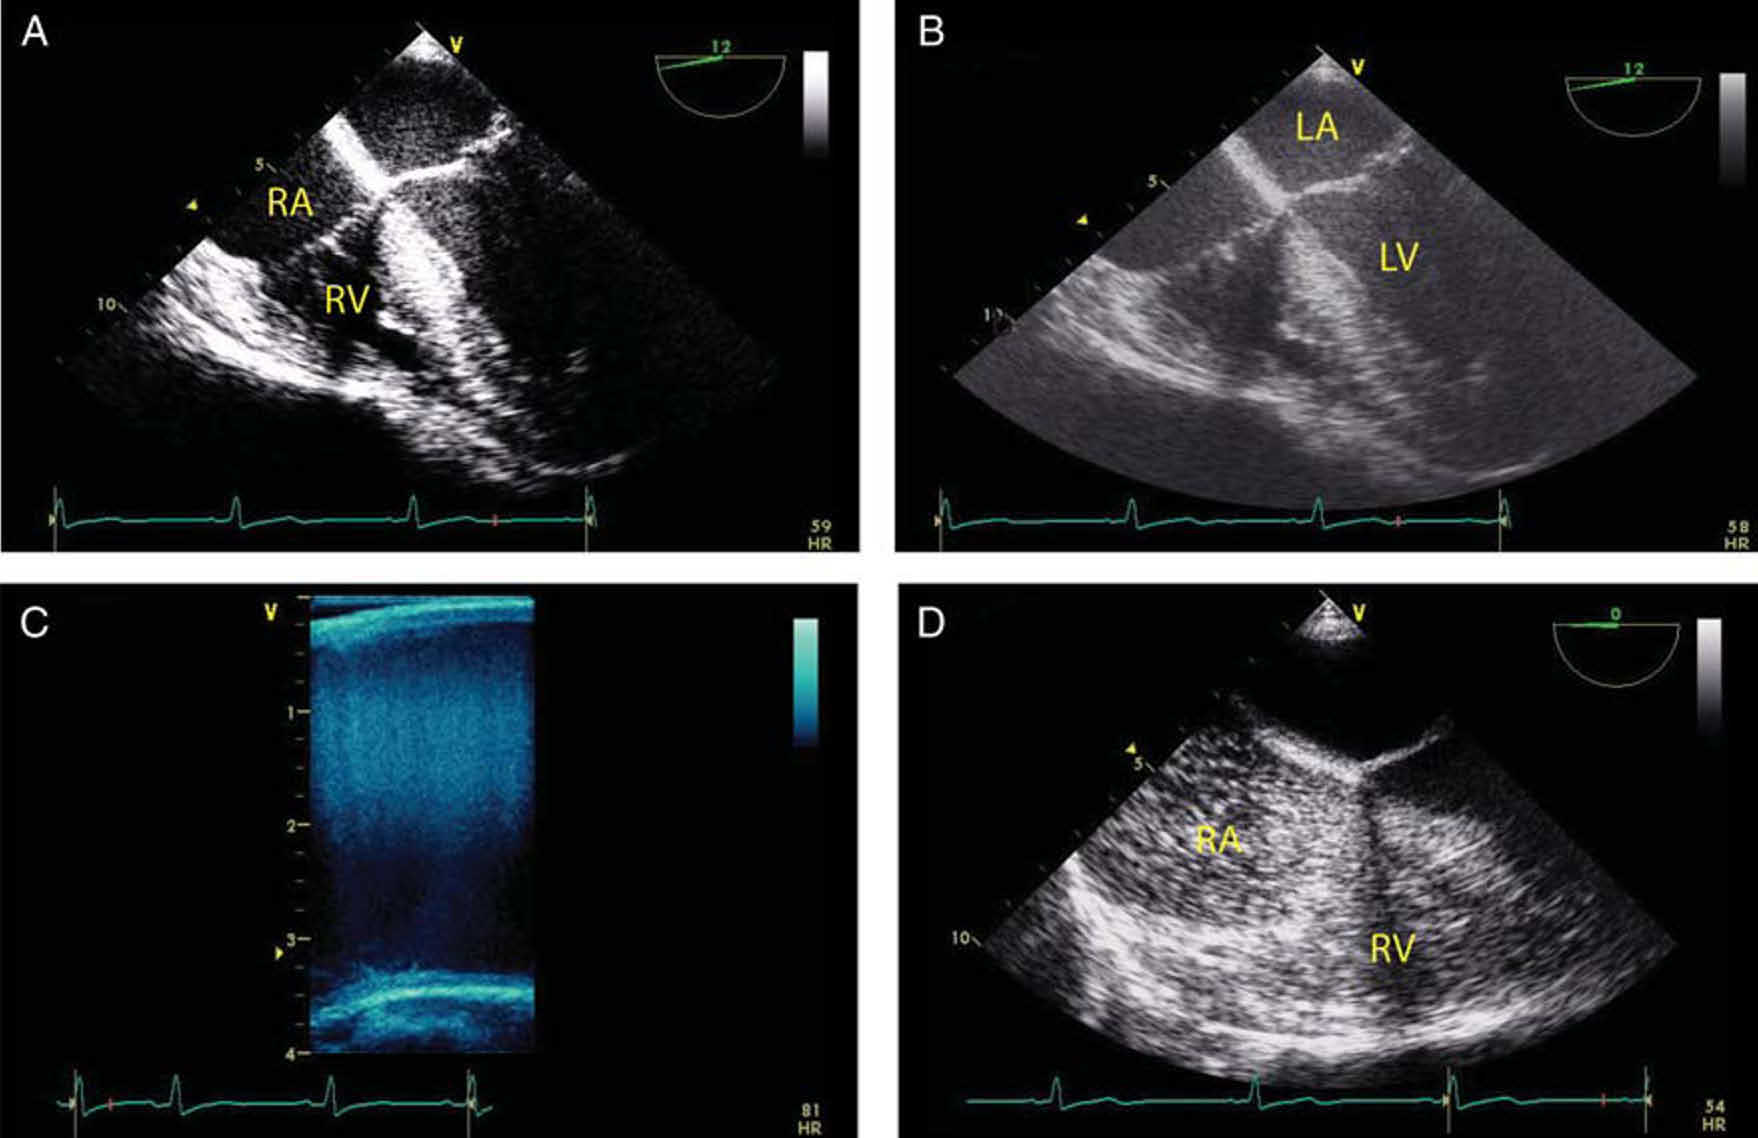

多普勒频移超过奈奎斯特极限会出现时间混叠(图 3C)。有三种主要方法可以提高时间分辨率,从而防止时间混叠:

此外,多普勒信息也可以显示在类似于上述解剖结构成像的彩色窗口(彩色多普勒模式)中(图 3D)。彩色窗口的每一帧都由重复的超声波脉冲形成。每一帧包含多条扫描线,每条扫描线都有多个脉冲(称为 ensemble length)。每条扫描线需要这些重复的脉冲提供足够的信息,包括确定反射体的移动方向、反射体的平均速度、功率和方差(速度分布),因此帧率极低。帧频由下面的公式决定:

动态范围压缩发生在信号处理器中,通过将较大的功率规定为最大值和将较小的功率规定为零值,来减小动态范围。高压缩、窄动态范围(例如 30 分贝)会产生高对比度的图像(图 4A)。相反,低压缩、宽动态范围(例如 60 分贝)会产生低对比度和许多灰色阴影的图像(图 4B)。对比度分辨率可以通过添加颜色来增强,因为人眼可以区分比灰色阴影更多的颜色阴影(图 4C)。

注射造影剂后,它们暂时停留在血液中,可以与心肌分开显示。之所以会出现这种现象,是因为气体中超声的阻抗与软组织中的明显不同。阻抗是密度和传播速度的乘积,空气中的阻抗较低,而软组织中的阻抗较高。当这种差异出现时,超声会被微泡强烈反射,从而提高对比度分辨率和感兴趣结构的可视化(图 4D)。